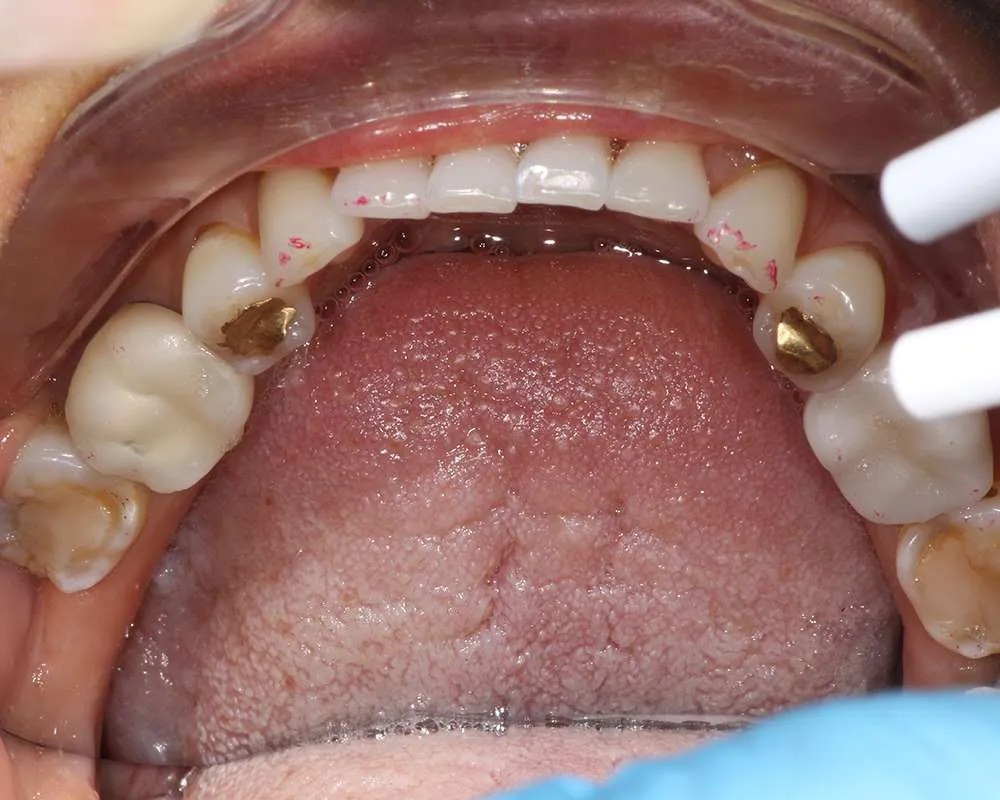

Real Stories, Real Results: Case Studies Showcasing How Our Personalized Approach Transforms Smiles and Lives

Complex Cases

Witness the Remarkable Changes We Can Achieve

The safe removal of mercury fillings is crucial for your health and well-being. At our practice, we follow strict protocols to ensure that mercury amalgam fillings are removed safely and effectively.